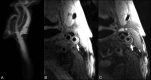

Identification of carotid artery atherosclerosis is conventionally based on measurements of luminal stenosis and surface irregularities using in vivo imaging techniques including sonography, CT and MR angiography, and digital subtraction angiography. However, histopathologic studies demonstrate considerable differences between plaques with identical degrees of stenosis and indicate that certain plaque features are associated with increased risk for ischemic events. The ability to look beyond the lumen using highly developed vessel wall imaging methods to identify plaque vulnerable to disruption has prompted an active debate as to whether a paradigm shift is needed to move away from relying on measurements of luminal stenosis for gauging the risk of ischemic injury. Further evaluation in randomized clinical trials will help to better define the exact role of plaque imaging in clinical decision-making. However, current carotid vessel wall imaging techniques can be informative. The goal of this article is to present the perspective of the ASNR Vessel Wall Imaging Study Group as it relates to the current status of arterial wall imaging in carotid artery disease.